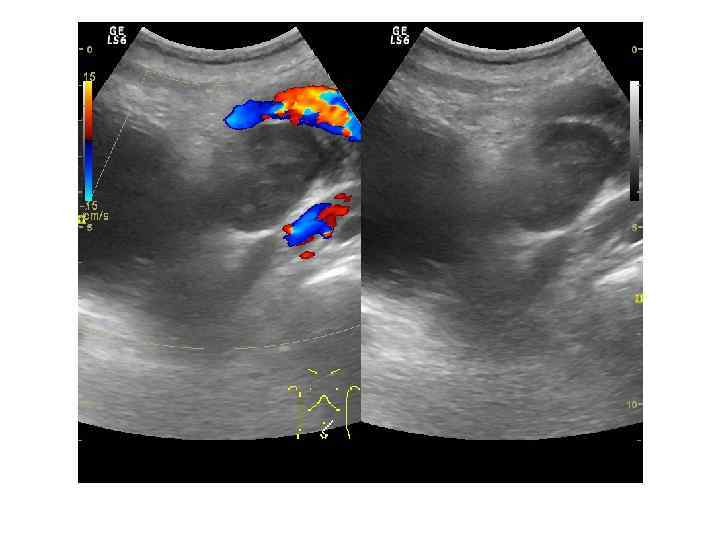

Прямые признаки опухоли: Наличие узла опухоли в железе (гипоэхогенные участки с неровными и нечеткими контурами неправильной формы в периферических зонах – 25%). Косвенные признаки: Асимметрия органа. Нарушение целостности капсулы. Деформация контура. Асимметрия семенных пузырьков.

Прямой признак наличия опухоли удается выявить только в 25 -30% случаев. В 65% эхогенность опухолевых узлов неотличима от прилежащей диффузно-измененной ткани. Только стадии Т 3 и Т 4 позволяют в 100% случаев уверенно определить наличие опухоли. При стадиях ниже Т 3 основываться только на ультразвуковую картину нельзя!

ЦДК и ЭДК опухолевого поражения простаты Большинство авторов отмечает усиление и асимметрию сосудистого рисунка в зоне опухолевого роста.